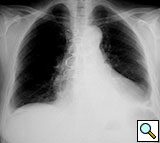

Figure 12. Postoperative sternal reconstruction showing sternal fixation with DSS (2 and 3 units in the right and left hemisternum, respectively